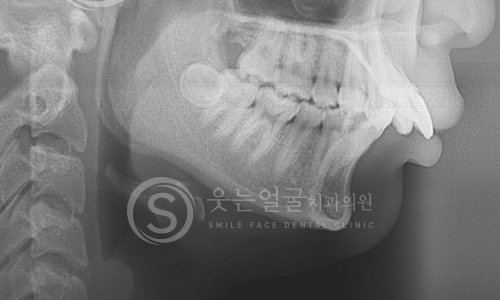

02 파노라마 촬영

03 세팔로 촬영

04 턱관절 검사

05 정면 X-ray 촬영

웃는얼굴치과의 12단계 교정진단시스템은 환자의 치아와 턱 구조,

얼굴 균형, 교합 상태 등을 체계적으로 분석하여

최적의 치료 계획을 수립하는 첨단 진단 프로세스입니다.